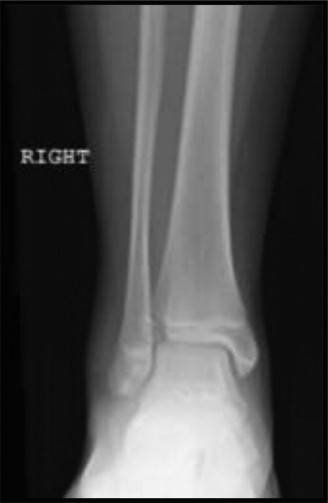

Potential for other intra-articular pathology with tibial tubercle fractures? CASE 10 You are called to the emergency room to evaluate a 13-year-old male complaining of acute right ankle pain. He reports that he injured his ankle earlier in the day when another player “took him out” during a soccer match. He was unable to bear weight through the right lower extremity and was brought promptly to the hospital for evaluation and management of his injury. An anteroposterior radiograph of the patient’s ankle is shown in Figure 10–14.

Figure 10–14

The correct answer is (B). The radiograph shown demonstrates a Tillaux fracture, the eponym used to describe transitional ankle fractures in adolescents characterized by two main fragments: one fragment being the anterolateral distal tibial epiphysis and the second including the tibial metadiaphysis, the physis, and the posteromedial epiphysis. On an anteroposterior radiograph, the fracture line appears to run through the physis and exit through the epiphysis. The anatomic structure attached to this piece is the anterior inferior tibiofibular ligament (AITFL), one of the primary syndesmotic ligaments of the ankle. Chopart injuries involve the midtarsal joint. The Chaput fragment is another eponym (used more commonly in adult ankle fractures) to describe the fracture piece that remains attached to the AITFL. The anterior talofibular ligament (ATFL) is the most commonly injured structure in lateral ankle sprains.

After reviewing the patient’s radiographic imaging, you diagnose an injury involving the growth plate of the distal tibia. Which of the following answers correctly pairs the description of this injury with its associated Salter–Harris fracture classification?

The correct answer is (D). The Salter–Harris classification system for describing fractures in skeletally immature individuals is as follows: Salter–Harris I fractures involve the growth plate only and are not usually evident on plain radiographs. This is usually a clinical diagnosis. Salter–Harris II injuries involve the physis (growth plate) and then the fracture line “exits” into the metaphysis (away from the joint).

This metaphyseal fragment is often called a “Thurston–Holland” fragment. Salter–Harris III injuries involve the physis and then the fracture exits into the epiphysis (towards the joint). The injury depicted in Figure 10–14 is a Salter–Harris III. Salter–Harris IV injuries involve the growth plate, with extension of the fracture into both the epiphysis and metaphysis. Salter–Harris V injuries are crush injuries through the growth plate that are often radiographically indistinguishable from Salter–Harris I injuries initially, but have higher rates of physeal arrest due to the increased force that produces this injury.